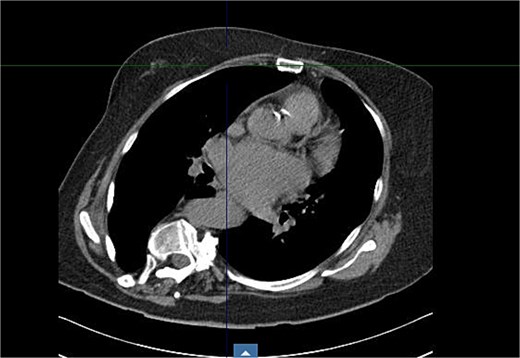

Preoperative imaging highlighted this significant spinal deformity and its impact on cardiac orientation and accessibility (Fig. 3). The scoliosis increased the complexity of the surgery, necessitating customized operative strategies. The patient underwent minimally invasive MVR and septal myectomy through a right mini thoracotomy. A mechanical valve was selected as a redo would be near impossible due to the cases uniqueness and inherent difficulty. Operative technique involved a 5 cm skin incision on the right upper breast at the 2nd ICS for a working port (Fig. 4), with additional ports in the 2nd and 4th ICS for camera and CO₂ venting. Extracorporeal circulation was established via femoral–femoral bypass through a groin incision to access the left femoral vessels for cannulation.

Intraoperative findings included an overinflated right lung, left-rotated and enlarged heart, and a severely dilated atriua. There was evidence of pulmonary hypertension with dilated pulmonary arteries. The mitral valve displayed fibroelastic degenerative disease with very thin leaflets and multiple chordal ruptures on P2. The annulus, though not calcified, was notably dilated. LV function was mildly reduced, the left appendage was free of thrombi, and the septum was hypertrophic and fibrotic.